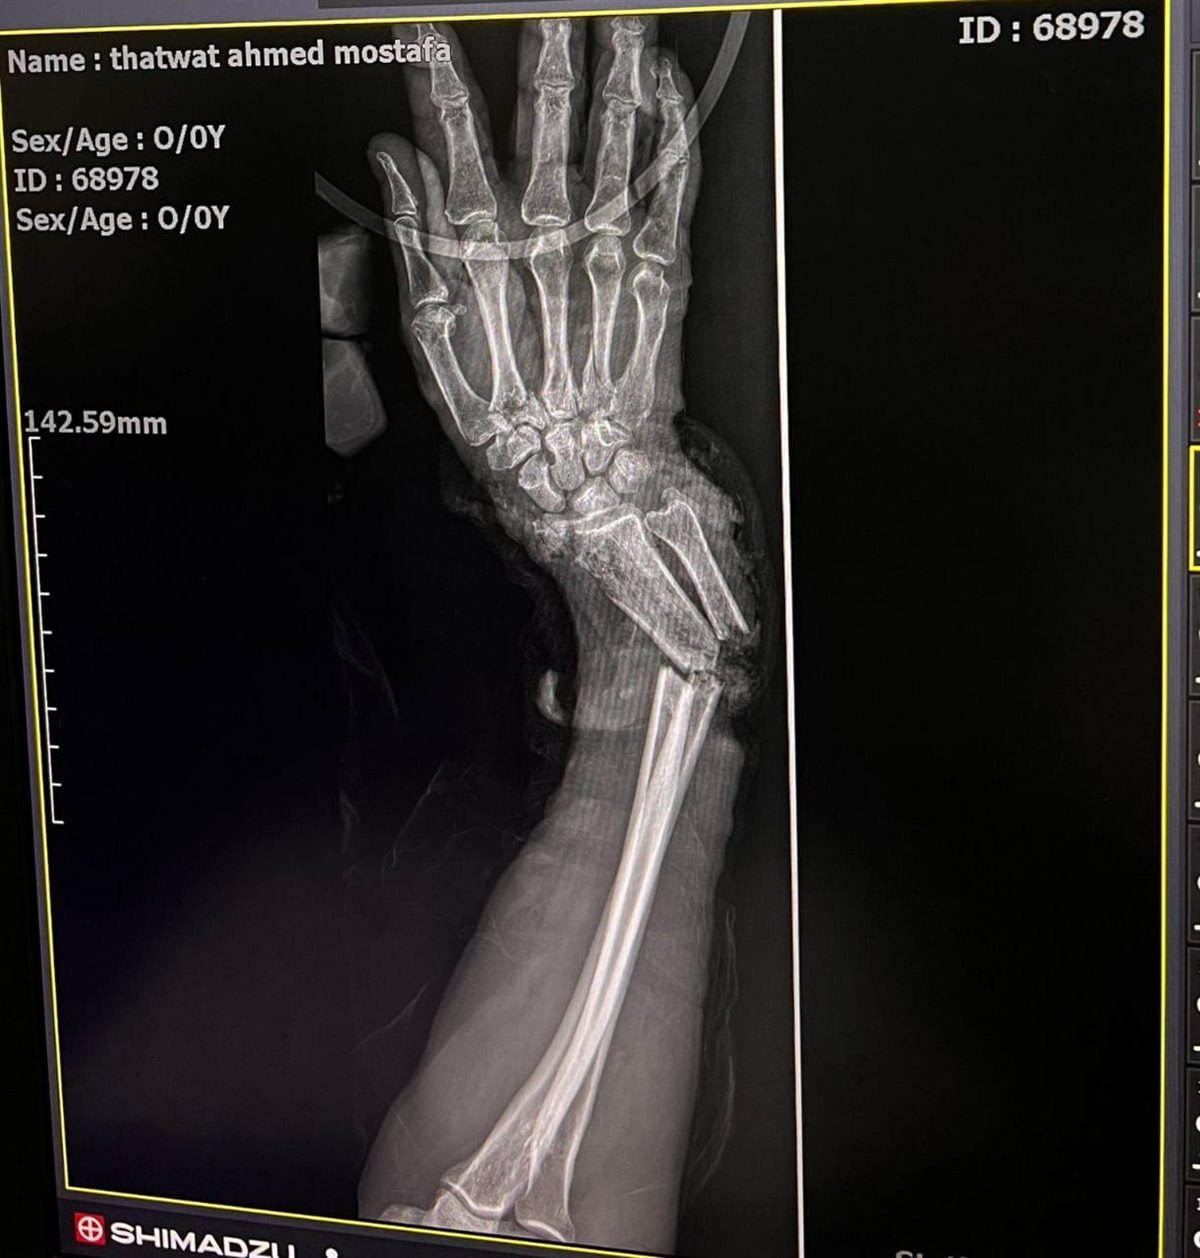

وقال الدكتور ياسر عثمان مدير وحدة الجراحات الميكروسكوبية أن التنسيق بين الفرق المختلفة كان عنصرًا حاسمًا في نجاح التدخلين، موضحاً ان الحالة الأولى كانت لمصاب يبلغ ٥٢ عامًا أصيب في حادث قطار، نتج عنه بتر أسفل الساعد الأيمن مع قطع كامل للأوتار والشرايين والأعصاب، إضافة إلى كسر مضاعف بالكعبرة والزند، وقد تم خلالها إعادة توصيل الأوتار والأعصاب والشرايين وتثبيت الكسور بواسطة شريحة ومسامير، والحالة الثانية لمصاب يبلغ ٢٣ عامًا تعرض لحادث سيارة أدى إلى بتر أعلى العضد الأيسر وقطع تام للشرايين والأعصاب والعضلات مع كسور مضاعفة بالساعد، وتم خلالها تثبيت الكسور وإعادة توصيل الشريان العضدي باستخدام رقعة وريدية